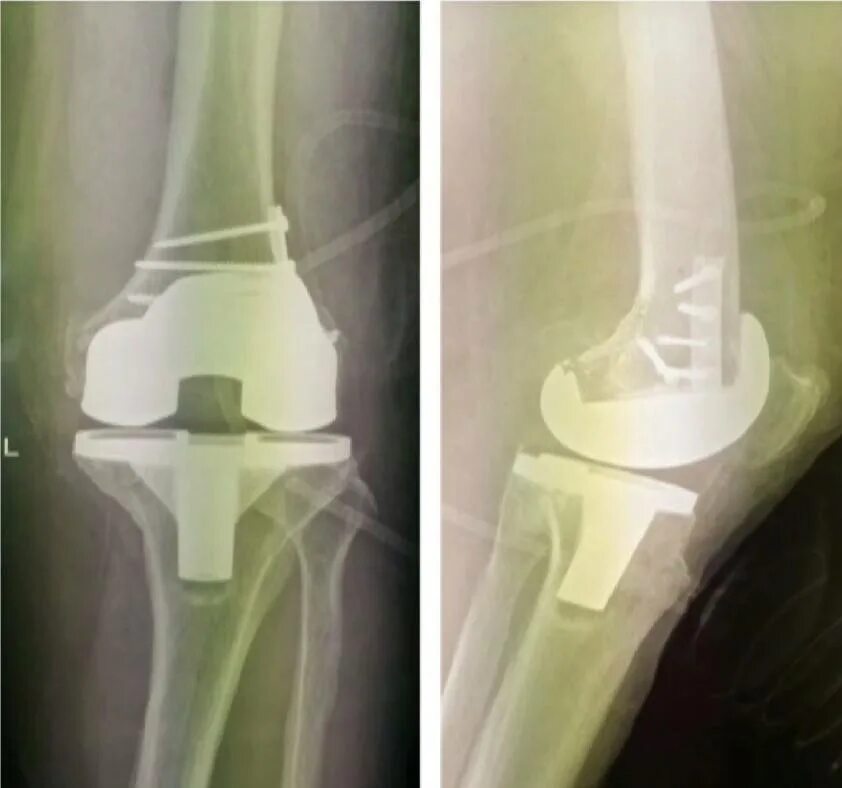

В каком случае меняют сустав